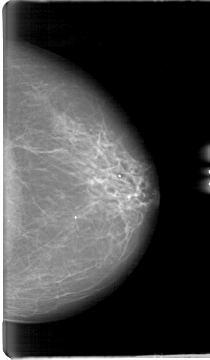

D_4068_1.LEFT_MLO

LEFT_MLO LINES 5386 PIXELS_PER_LINE 3226 BITS_PER_PIXEL 12 RESOLUTION 43.5 NON_OVERLAY